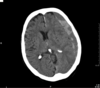

Subdural on CT head

143

Left subdural with some midline shift